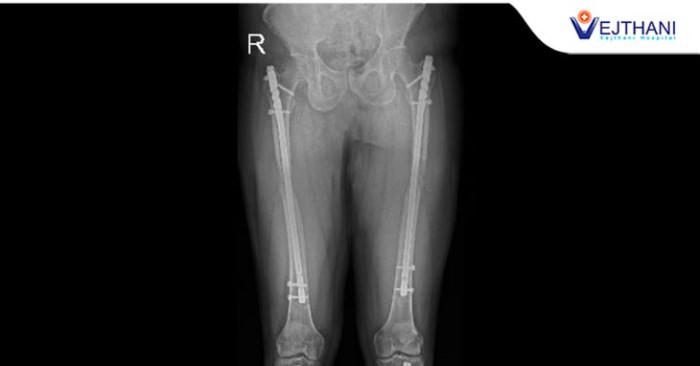

Orthopedics Center

Limb Lengthening at Vejthani Hospital in Thailand

Limb lengthening is performed at Vejthani Hospital in Thailand for patients who have bone discrepancy, abnormalities or skeletal dysplasia.